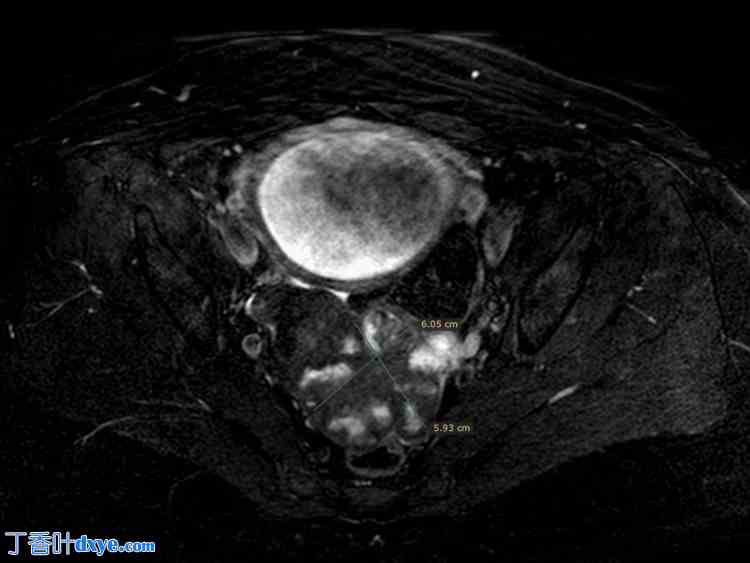

患者是一位49岁的女性,三年前曾接受腹腔镜下切除一个10厘米FIGO 4级(国际妇产科联合会4期)纤维瘤的手术。她来院门诊进行常规妊娠监测,超声检查显示盆腔内有一个6x6厘米的菜花状肿瘤。为了更好地观察肿瘤及其与周围结构的关系,患者在妊娠28周时接受了磁共振成像(MRI)检查(图1、图2)。

图2. 妊娠28周MRI检查结果:肿瘤大小及位置(轴状面)。

MRI,磁共振成像。